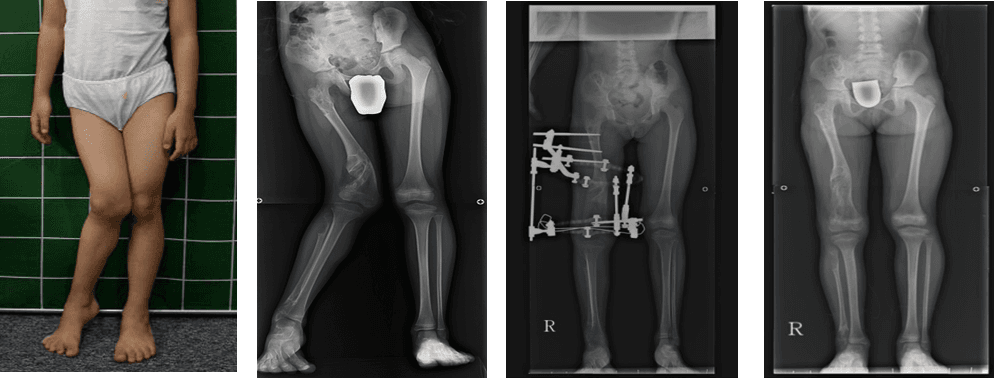

The right leg, which was curved inward, was corrected at the femur.

Perform correction surgery on the right leg that has varus deformity at femur.